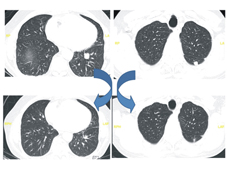

上圖:免疫治療前,發現有肺部轉移。

下圖:免疫治療後,肺部轉移病灶明顯縮小。